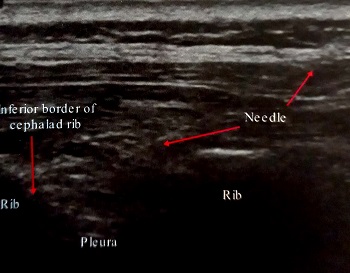

تصویر سونوگرافی سوزن در محل عصب اینترکوستال